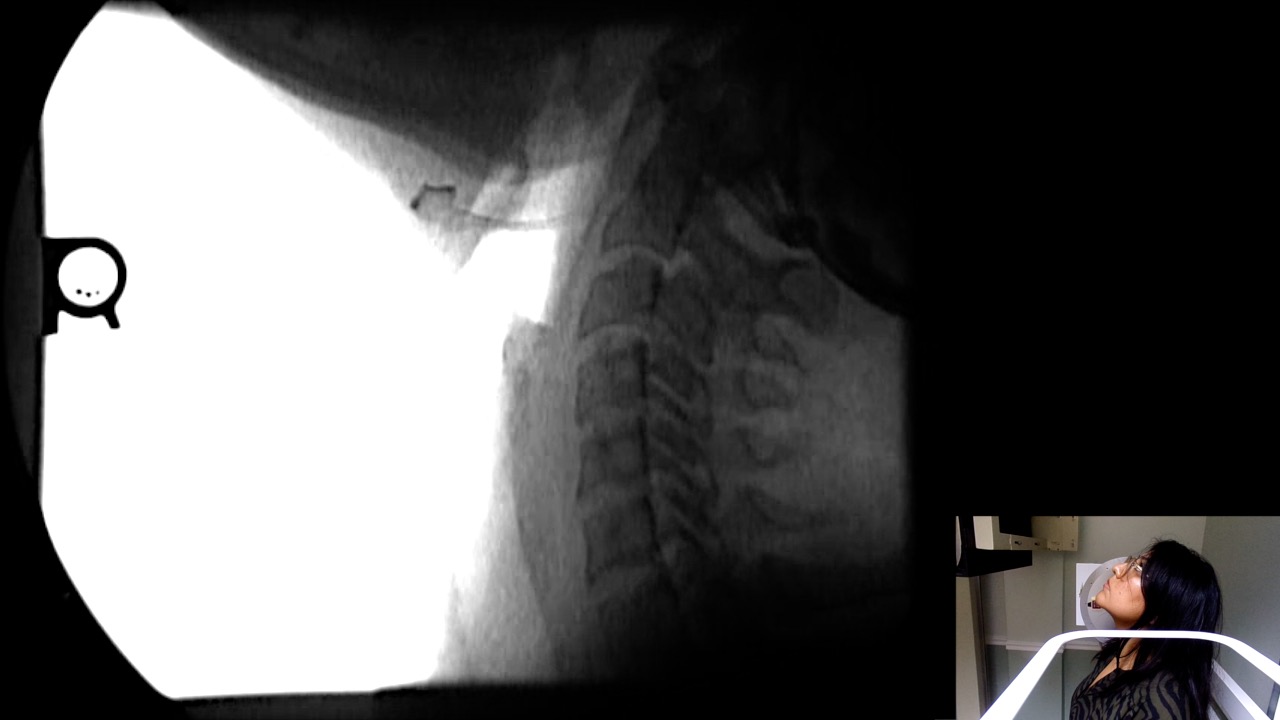

Image Name Image Type Image

Calibrate Image